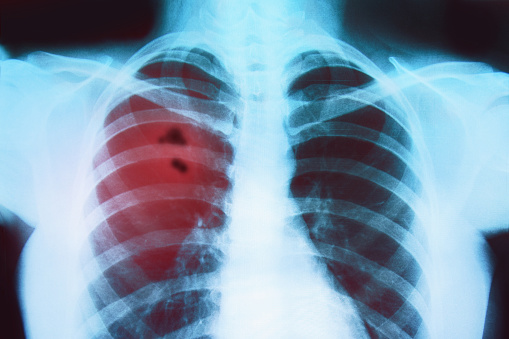

RAKOVINA - PLÍCE -přírodní pomoc+léčba půstem, bylinami+bio-informační medicínou

/rada pro paní jejíž muž byl nemocen rakovinou a metastázami na plicích-výňatek z mé odpovědi pro ni/

-toto mu bude dávat do kupy střeva, mimo toby si měl dát i aspoň 3 - 5 dní zcela bez jídla jen popíjet čaje z výše jmenovaných bylin+mezi to si dát místo jídla 6-8x denně po 1 dcl výše jmenovaných zeleninových šťáv-doplní mu to minerály a vitamíny do těla, zažene to pocit hladu+vždy po 15 min. po té deci směsky šťáv si dá 2-3dcl odvaru z léčivých bylin -po těchto 3 dnech, by měl začít jen se zdravou stravou, bez zbytečných bílkovin-omezit maso-jen 1x za 3 dny vařené maso-krůtí, kuřecí, libové hovězí, mimo to smí jíst masové vývary-dlouho vařené z masa+kostí+větší množství zeleniny+koření+libeček+necháte asi 4 hodiny na mírném ohni vařit-toto pak smí, jen se zeleninou+bez masa u toho půstu, a po něm to smí i s masem,ale bez nudlí, či jiných přídavků-je to lék pro něj na střeva a obnovu střev+dodá tím tělu všechny potřebné minerály a vitamíny, ale tuhou stravu musí si vynechat co nejvíce-pečivo vůbec NESMÍ-PO 45 DNÍ, jen z bezlepkového pečiva snad by mohl, máslo omezit na minimum, sýr byste mu měla dělat doma z kýšky= 1 litr kýšky-přilijete vařící vodu k tomu do hrnce, necháte si ustát až do vychladnutí, pak scedíte si tu vodu-TU BUDE MANŽEL POPÍJET MEZI tím, co nebude pít čaje nebo šťávu-dává to do normálu střeva, žaludek, játra,ledviny-obnovuje to správnou funkci trávicích orgánů+žaludku a žlučníku, sleziny a slinivky-takže to musí-a ono je to docela chutné, takže se toho nemusí bát, no a ten scezený-tvaroh z té kýšky, pak smí trochu posolený jíst s tím bezlepkovým chlebem. maso tedy jen ryby, kuřecí, krůtí, hovězí vařené-pokud cokoliv mu budete dělat tak bez omáček, cibule nebo česneku-aby se mu nedráždil trávicí trakt-no a hlavně- DENNĚ SE UVOLNĚNĚ KLIDNĚ BUDE PRODÝCHÁVAT=uvolněný klidný výdech na počítání 1,2,3+pak uvolněný a klidný NÁDECH na 1,2,3,+toto 5x denně nejlépe venku-balkon nebo otevřené okno nebo pokud smí krátké procházky, či pobyt venku na lavičce, či zahradě+soustředit se jen na své uvolněné dýchání, pravidelné, klidné v jeho tempu-tímto regeneruje svoje plíce+umožní lepší výměnu krve v plicích/hodila by se u něj i kyslíková terapie